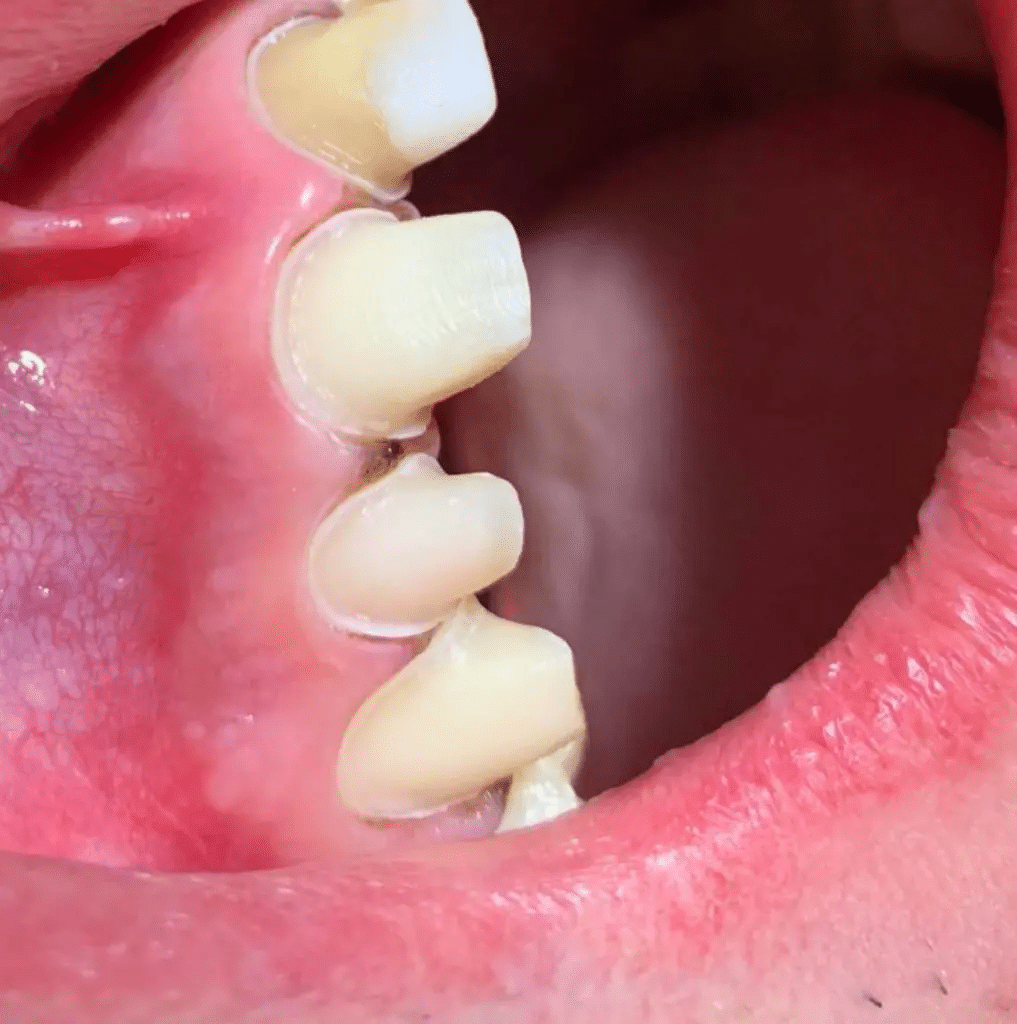

Druga posjeta – preparacija zuba na stepenik

Druga posjeta pacijenta započinje davanjem anestezije za zube koje brusimo. Za brušenje zuba na zaobljenu stepenicu koristimo odgovarajuće borere, različite širine i granulacije. Zube brusimo na način da zub bude cervikalno najširi, a prema incizalno/okluzalno plohe zuba da budu blago okomite jedna prema drugoj kako bi se izbjegla podminirana mjesta na zubu koja će onemogućiti nalijeganje buduće navlake na stepenicu i ugroziti rubno zaptivanje buduće navlake.

Stepenica treba da bude kontinuirana i iste širine. Stepenicu prvo pozicioniramo u nivou gingive, zatim postavimo retrakcioni konac u sulkus zuba i sačekamo da se gingiva retrahuje tj. povuče, pa stepenicu spustimo pola milimetra tako da rub buduće navlake bude ispod nivoa gingive. Ovo radimo zbog estetskog efekta. Kada smo spustili stepenicu 0.5-1 mlimetar ispod nivoa gingive, stavljamo drugi konac veće debljine i pristupamo uzimanju definitivnog otiska. Otisak se uzima A-silikonom na način da prvo odaberemo kašiku odgovarajuće veličine u koju nanosimo prvu masu i otiskujemo vilicu pacijenta. Zatim sačekamo par minuta dok se masa stvrdne, vadimo otisak iz usta pacijenta, operemo ga i posušimo pusterom.

U ovaj otisak nanosimo drugu masu tečnije konzistencije (korekturna masa), dok istovremeno skidamo retrakcioni konac oko zuba. Kada su konci skinuti i naglašeni sulkusi unosimo kašiku sa prvim otiskom i korekturnom masom i ponovo otiskujemo. Sačekamo 5 minuta da se korekturna masa veže i izvadimo otisak iz usta pacijenta. Ovaj otisak se naziva dvostruki korekturni otisak. Na otisku provjerimo da li su svi zubi dobro otisnuti i da li se vidi svaki stepenik. Nakon uzimanja otiska, registrujemo zagriz i zajedno sa pacijentom odredimo boju budućih navlaka. Nakon sto smo odredili boju pristupamo izradi privremenih navlaka i time završavamo drugu posjetu.